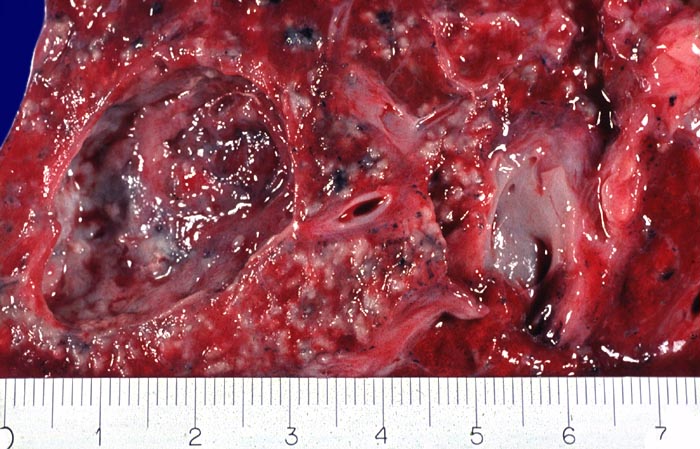

Das morphologische Bild ist äusserst variabel. Je nach Abwehrlage, Art und Geschwindigkeit der Ausbreitung entstehen unterschiedlich grosse, teils geschichtete Herde mit unterschiedlichem Grad an Epitheloidzellreaktion, zentraler Nekrose bzw. Vernarbung. Rein produktive Granulome ohne Nekrosen sind Zeichen guter Abwehrlage. Der Begriff Verkäsung bezieht sich auf den makroskopischen Aspekt von Nekrosen, der an Frischkäse erinnert. Exsudative nekrotisierende Granulome entstehen bevorzugt bei schlechter Abwehrlage. In späteren Stadien der Lungentuberkulose unterscheidet man produktive Phthisen mit azinös nodösen Gruppen von bronchogen entstandenen gering verkäsenden Streuherden (Präparat), zirrhotische Phthisen mit gering verkäsenden stark vernarbenden Herden und exsudative Phthisen bei schlechter Abwehrlage. Bei letzterer steht die Verkäsung im Vordergrund. Die bakterienreichen Herde entstehen teils hämatogen, teils bronchogen. Verkäsende Herde sind Ausgangspunkt für die Kavernenbildung. Kavernen stellen die wichtigste Quelle für die bronchogene Streuung dar.

• Tuberkulöse Herde ausgehend von vollständig oder partiell entzündlich zerstörten Bronchiolen in unmittelbarer Nachbarschaft von Arterien.

Makroskopie

Befund

Pathologischer Befund